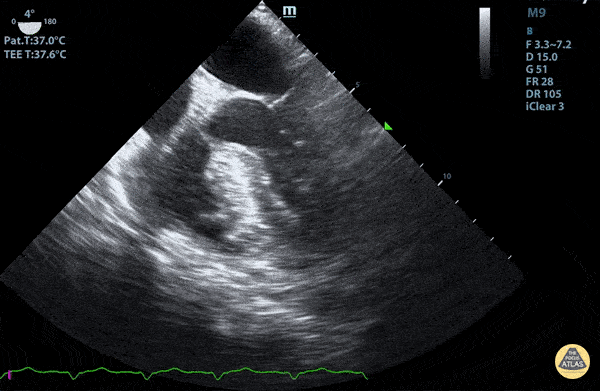

TEE - Mid-Esophageal 4 Chamber View  with a Trace Pleural Effusion

Mid-Esophageal 4 Chamber View with a trace pleural effusion Duncan McGuire, DO, Emergency Medicine, Beaumont Health